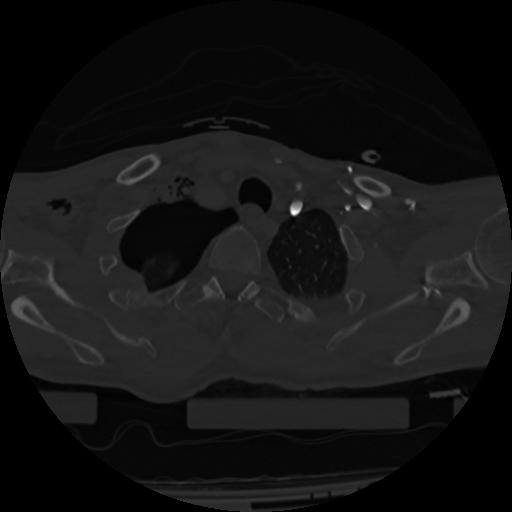

22 ANGIO,CE,Vol,0.5,ANGIO,,